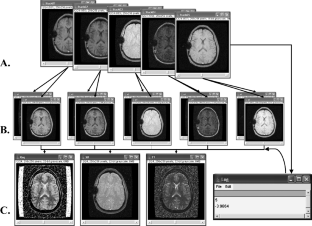

The demand for image-processing software for radiology applications has been increasing, fueled by advancements in both image-acquisition and image-analysis techniques. The utility of existing image-processing software is often limited by cost, lack of flexibility, and/or specific hardware requirements. In particular, many existing packages cannot directly utilize images formatted using the specifications in part 10 of the DICOM standard (“DICOM images”). We show how image analyses can be performed directly on DICOM images by using ImageJ, a free, Java-based image-processing package (http://rsb.info.nih.gov/ij/). We demonstrate how plug-ins written in our laboratory can be used along with the ImageJ macro script language to create flexible, low-cost, multiplatform image-processing applications that can be directed by information contained in the DICOM image header.